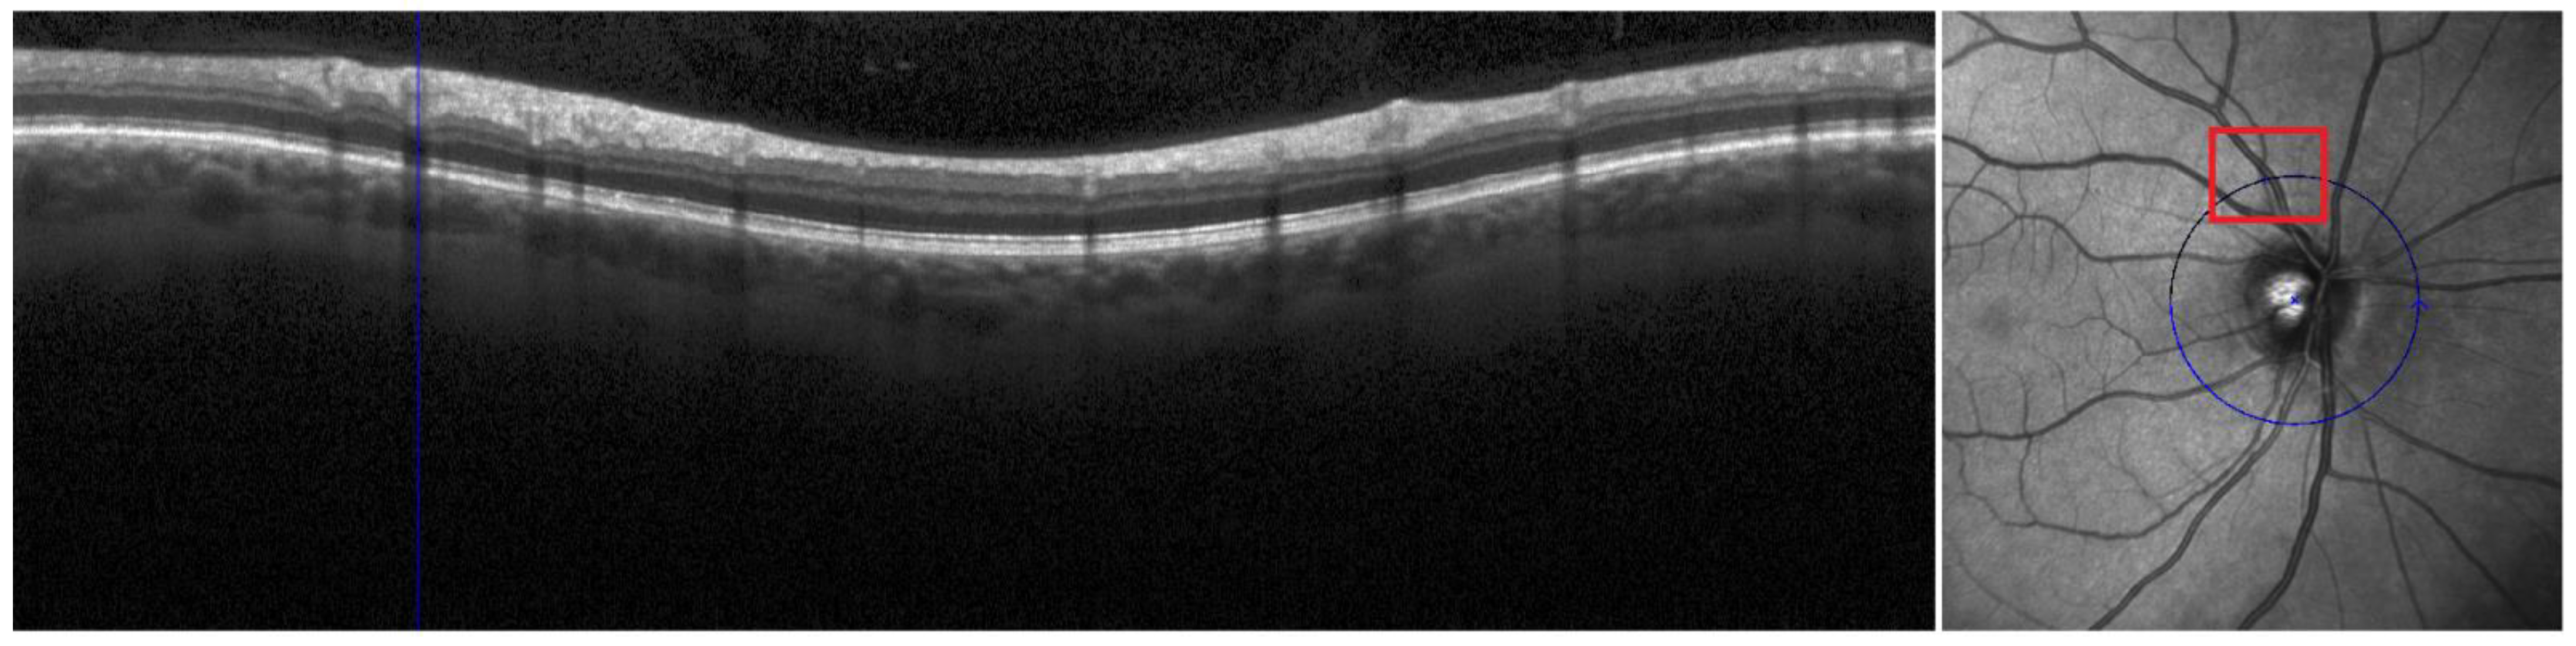

2.2. OCT Acquisition and Analyses